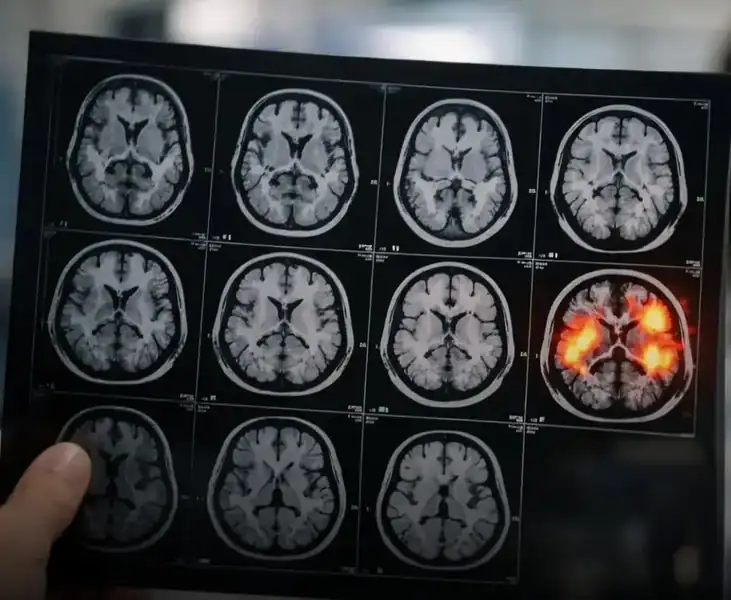

Uma das áreas que vem ganhando destaque na neurociência é o efeito da gratidão no cérebro humano. Pesquisas mostram que exercer regularmente a gratidão, como escrever diariamente três coisas pelas quais se é grato, pode ativar regiões cerebrais associadas à recompensa e ao bem-estar, fortalecendo conexões neurais ligadas à emoção positiva e motivação.